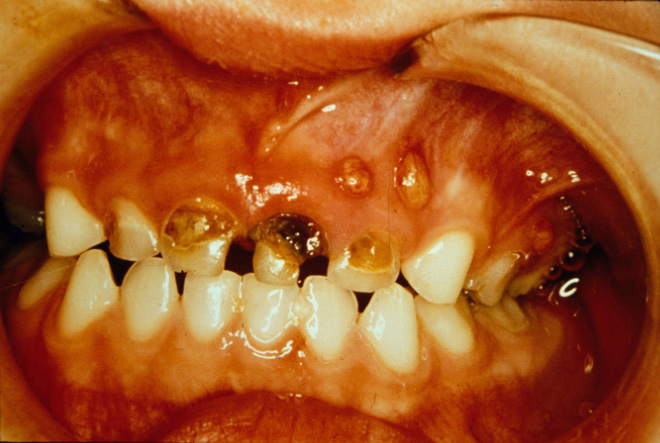

Although state definitions of neglect vary considerably, all specify acts of omission, including failure to provide adequate care, support, nutrition, shelter, and medical or other care necessary for a child’s health and well being.1 Parents who cannot access or finance dental care may not be neglecting their children. However, if resources are available and the child is not receiving proper care, a suspected case of neglect should be reported (Figure 13). According to the American Academy of Pediatric Dentistry, “dental neglect is a willing failure of parent or guardian to seek and follow through with treatment necessary to ensure a level of oral health essential for adequate function and freedom from pain and infection.”23 Because neglect may involve many factors, including money, insurance, transportation, and access to care, deciding to report suspected neglect may take more consideration than a suspected abuse case.

Figure 13. Dental neglect as indicated by multiple paruli from gross caries.

Figure 13